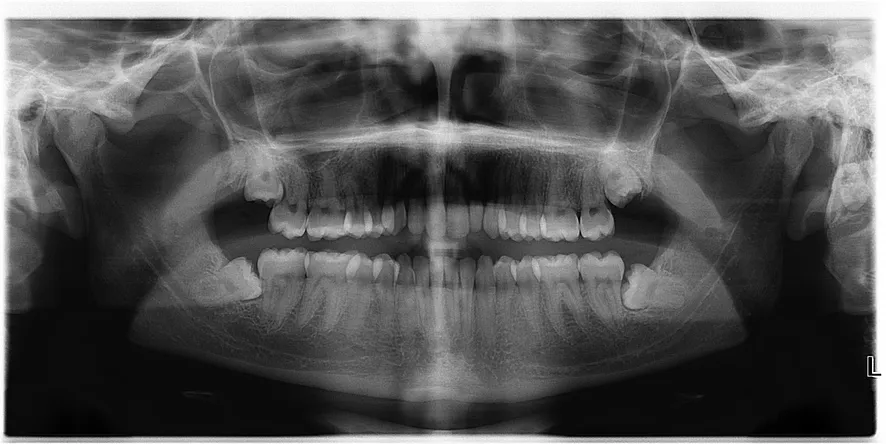

Wisdom Teeth X-Ray

Wisdom teeth are the third and final set of molars that emerge, usually during your late teens to early twenties. For some people the wisdom teeth emerge through the gums and have enough room to grow in naturally. For others, wisdom teeth often cause problems as they are trying to protrude through the gums. When a wisdom tooth is impacted the tooth is coming in at an angle and not straight through the gum line. This can cause pain, the tooth can come in unevenly, or the tooth may only emerge partially.

Impacted wisdom teeth can cause structural damage to the jaw and other teeth. They can also provide a place for bacteria to gather since they are hard to reach and clean. These potential problems make it necessary to remove impacted wisdom teeth so that larger problems do not arise. Routine x-rays during a dental exam can reveal if you will need to have your wisdom teeth removed.